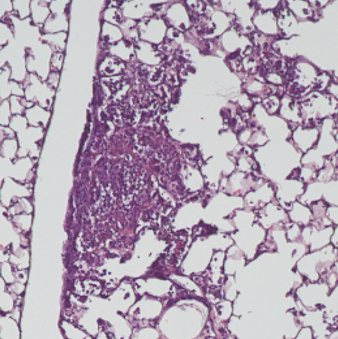

Scientists from Weill Cornell Medicine and the College of Agriculture and Life Sciences infected a group of mice with P. aeruginosa and another with P. aeruginosa combined with 2,3-butanediol. After three days, the mice with both factors had more than 100 times more of the bacteria in their lungs. The inability to eradicate the 2,3-butanediol-laden bacteria suggests why P. aeruginosa has posed such a significant problem for cystic fibrosis patients.